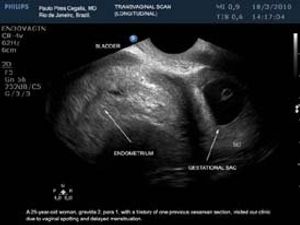

This is a confirmed case of scar ectopic pregnancy. Yesterday, I carried out this exam in an emergency room, without much time to perform an adequate sonogram, the patient did not feel good with “cramps” but no signs of bleeding.